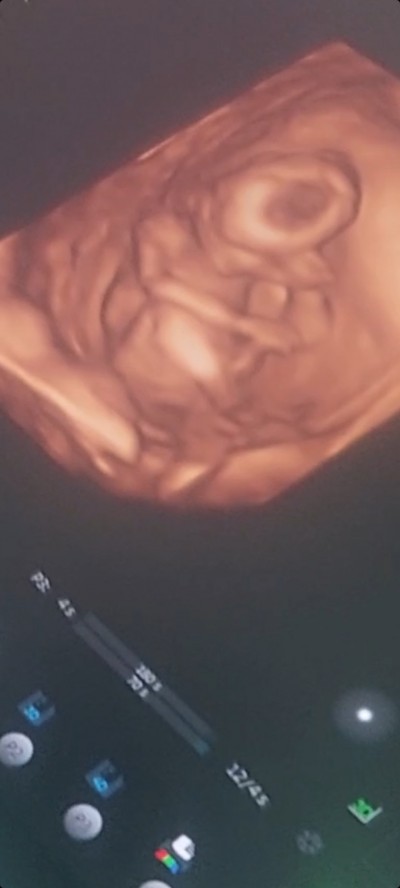

16+3 günlük hamileyim   4d ultasyon girdim doktora sormayi unuttum eve gelip vidyoyu izlyince farkettim bebegin basinin tepesinde siyahljk var bu haftalarda sac olurmu yada nedir bilgisi olan varmi yorumlarmisinz ? Endiseliyim

Gebelik haftası 16+3

Ultrason yanılmasıdır büyük ihtimalle tehlikeli birşey olsa doktor mutlaka söylerdi

Ultrasonlarda bu tarz yansımalar olur işi titresimlerine göre yansıdığı için görüntü böyle golgeler diyeyim çıka biliyor önemli birşey değil orda birşey olduğu için o siyahlık çıkmamış endişelenmeyin lutfen

Muhtemelen golgedir o gozuken. Cok icinize sinmiyorsa doktorunuza mesaj atin size aciklama yapar zaten. Saglikla dogsun inşallah

Bıngıldak yeri olabilir orası en son kapanır diye biliyorum 4d ultrason olduğu için daha net görmüş olabilirsiniz yine de Bir doktora danışın isterseniz